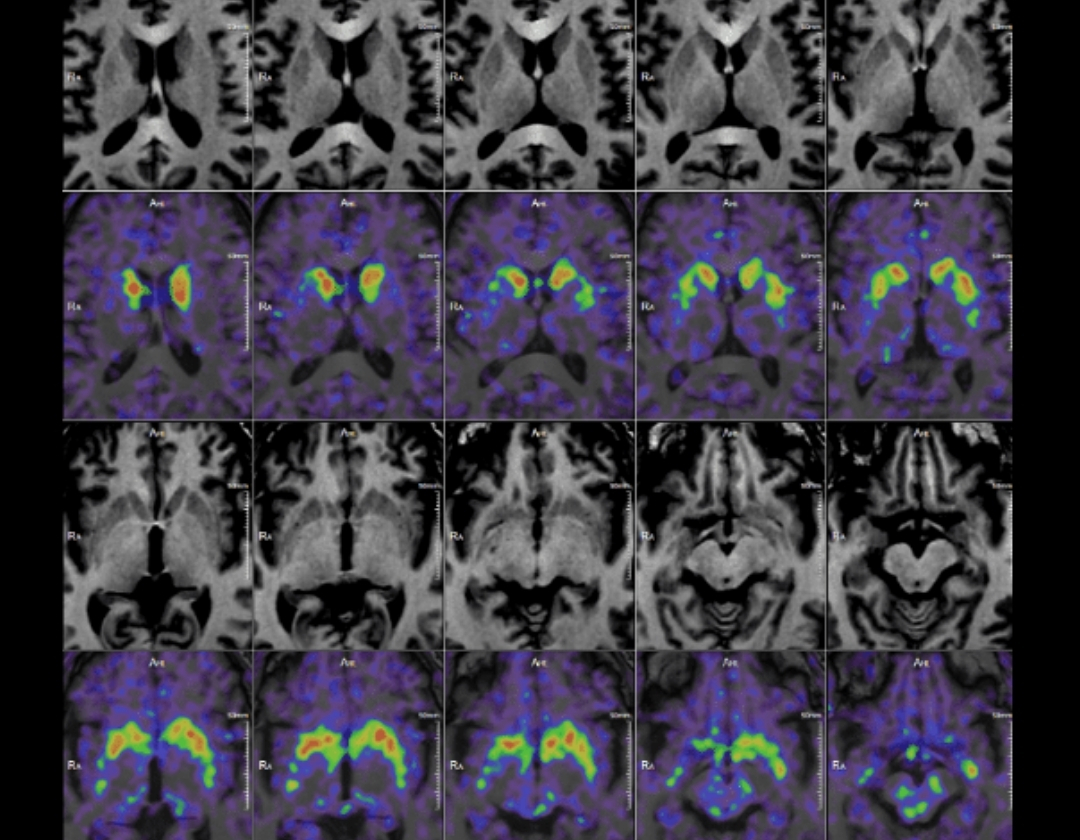

MF-DOPA used for diagnosing Parkinson's disease populations